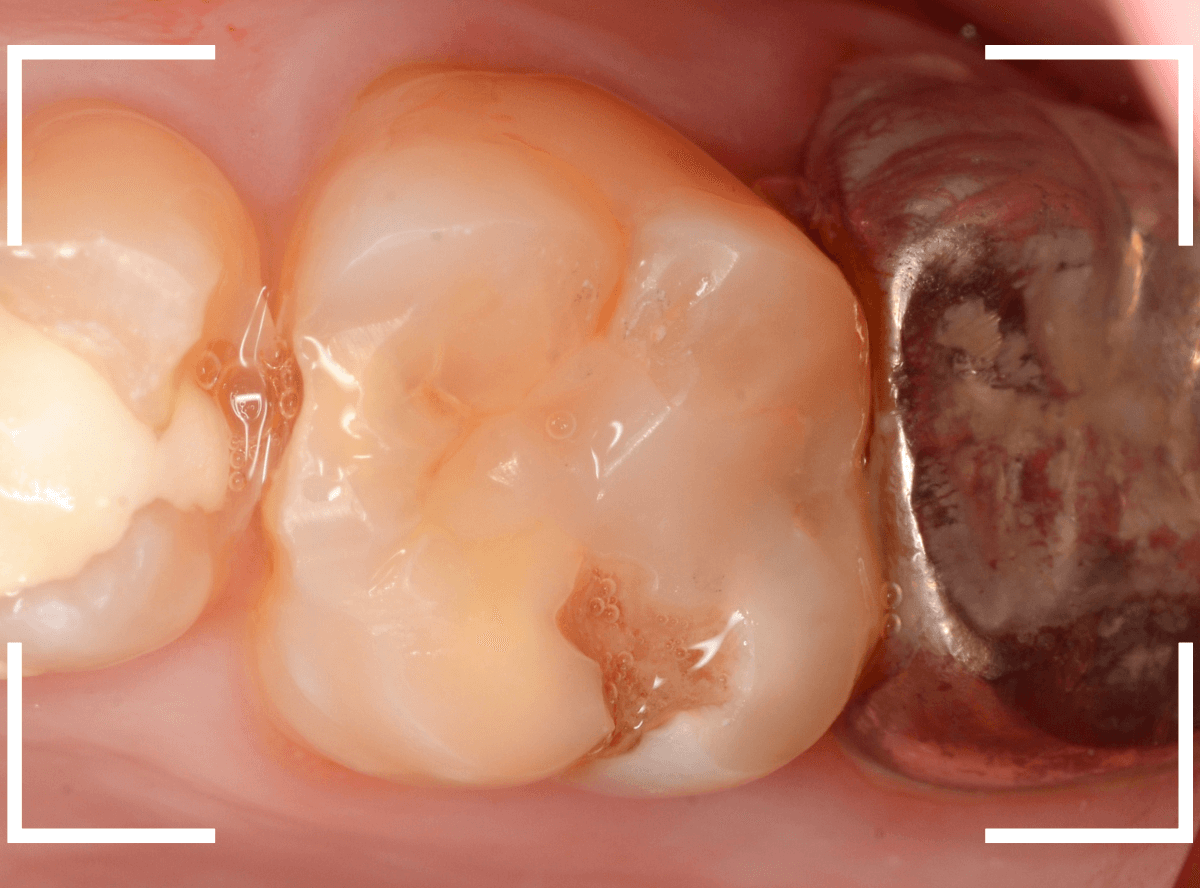

こちらは、下の奥歯の写真です。

特に症状の訴えはありませんでしたが、

歯を観察した瞬間、「虫歯がありそうだな」と思われるような所見です。

私の目には大体このように映っています。

レントゲン写真です。

私が虫歯っぽいと思っていた部分よりも、むしろ手前の部分に大きな虫歯がありました。

もう神経に触りそうな大きな虫歯です。

これだけの虫歯であれば、通常であれば、歯がしみたり、食事中に痛みがあったり何らかの症状があるのですが、無症状のこともあります。

麻酔をして治療開始です。

少し削ると、大きな虫歯が出てきました。

手前の歯にもかかる大きな虫歯でした。

ここまで削っても、まだ、虫歯が残っています。

すぐ下には歯の神経が来ていますから、より慎重に虫歯を除去します。

露髄(歯の神経が見えてしまう事)に怯えながら、慎重に虫歯を除去しました。

なんとか神経ギリギリのところで虫歯がとどまっていました。

虫歯を完全に除去した後、お薬とセメントをつめて経過観察です。

かなり大きな虫歯でしたが、おそらく神経の治療をせずになんとかなりそうです。。。